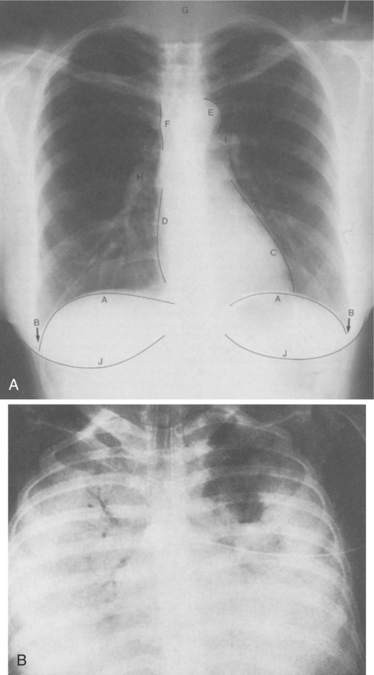

In flail chest, the paradoxical chest motion impairs movement of gas in and out of the lungs (Fig. 15-13), promotes atelectasis, and impairs pulmonary drainage. Other clinical manifestations of flail chest include excruciating pain, severe dyspnea, hypoventilation, cyanosis, and hypoxemia, leading to respiratory failure without the appropriate intervention.

Figure 15-13 Flail chest. Arrows indicate air movement or structural movement. A, Flail chest consists of fractured rib segments that are detached (free-floating) from the rest of the chest wall. B, On inspiration, the flail segment of ribs is sucked inward. The affected lung and mediastinal structures shift to the unaffected side. This compromises the amount of inspired air in the unaffected lung. C, On expiration, the flail segment of ribs bellows outward. The affected lung and mediastinal structures shift to the affected side with the diaphragm elevated on that side (not shown). Some air within the lungs is shunted back and forth between the lungs instead of passing through the upper airway.

Atelectasis is suspected in penetrating or other chest injuries. X-ray examination may show a shadow in the area of collapse. If an entire lobe is collapsed, the radiograph will show the trachea, heart, and mediastinum deviated toward the collapsed area, with the diaphragm elevated on that side (see Figs. 15-13 and 15-22). Chest auscultation and physical assessment add to the clinical diagnostic picture. Blood gas measurements may show decreased oxygen saturation.